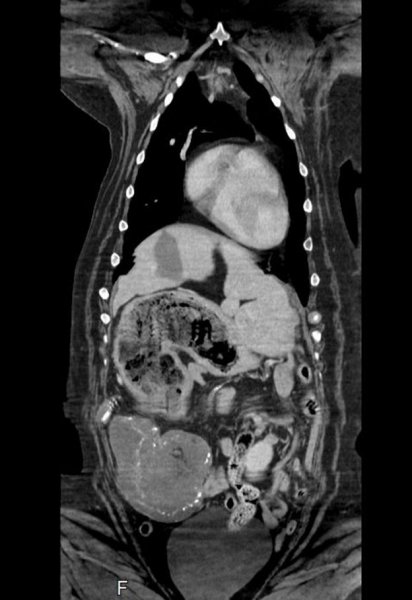

Хозяева восьмилетней Мэйси обратились в ветеринарную клинику с жалобами на ее самочувствие. Врачи провели компьютерную томографию и увидели, что ее желудок и селезенка раздулись до огромных размеров. Ветеринары предположили, что у питомца рак, и с согласия хозяев отправили его на операцию по удалению селезенки.

Однако во время операции ветеринар Ник Блэкберн (Nick Blackburn) обнаружил, что селезенка у Мэйси здорова, а «опухоль» со снимка оказалась четырьмя целиком проглоченными мягкими игрушками. «Это явно не то, что мы ожидали увидеть. Мы все знаем, что собаки любят пожевать то, что жевать не стоит, но проглотить четыре игрушки целиком еще ухитриться надо», — отметил он.